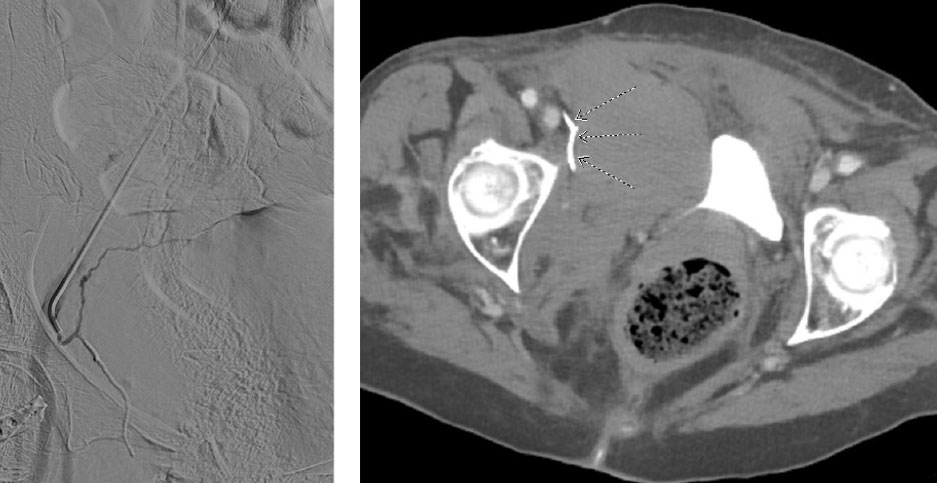

90-year-old female presented to the emergency room as a trauma alert after a fall from standing. Pertinent PMH of atrial fibrillation on Eliquis. Patient reporting abdominal and right hip pain. Noted to be hypotensive upon arrival with systolic pressures in the 70s. Massive transfusion protocol (MTP) initiated. CT of the abdomen and pelvis obtained demonstrating a comminuted fracture of the right superior pubic ramus with active arterial bleeding noted in the adjacent pelvic musculature (CT image 1, arrows). IR consulted for angiogram with possible embolization.

Scan images from Obsidio case.